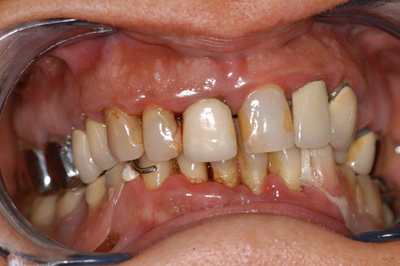

Réabilitation globale 1

Des problèmes de gencives, saignements etc.

Un appareil remplace des dents du bas, et n’est plus ajusté. Il bouge beaucoup, lui fait mal et elle ne le supporte plus.

Le traitement : remise en état des tissus gingivaux, élimination des dents “fichues”, réalisation de couronnes et bridges céramo-métalliques au maxillaire.

A la mandibule : extraction des dents restantes et pose immédiate de 6 implants en même temps que la pose d’un bridge provisoire.

Durée du traitement : huit mois

Avant